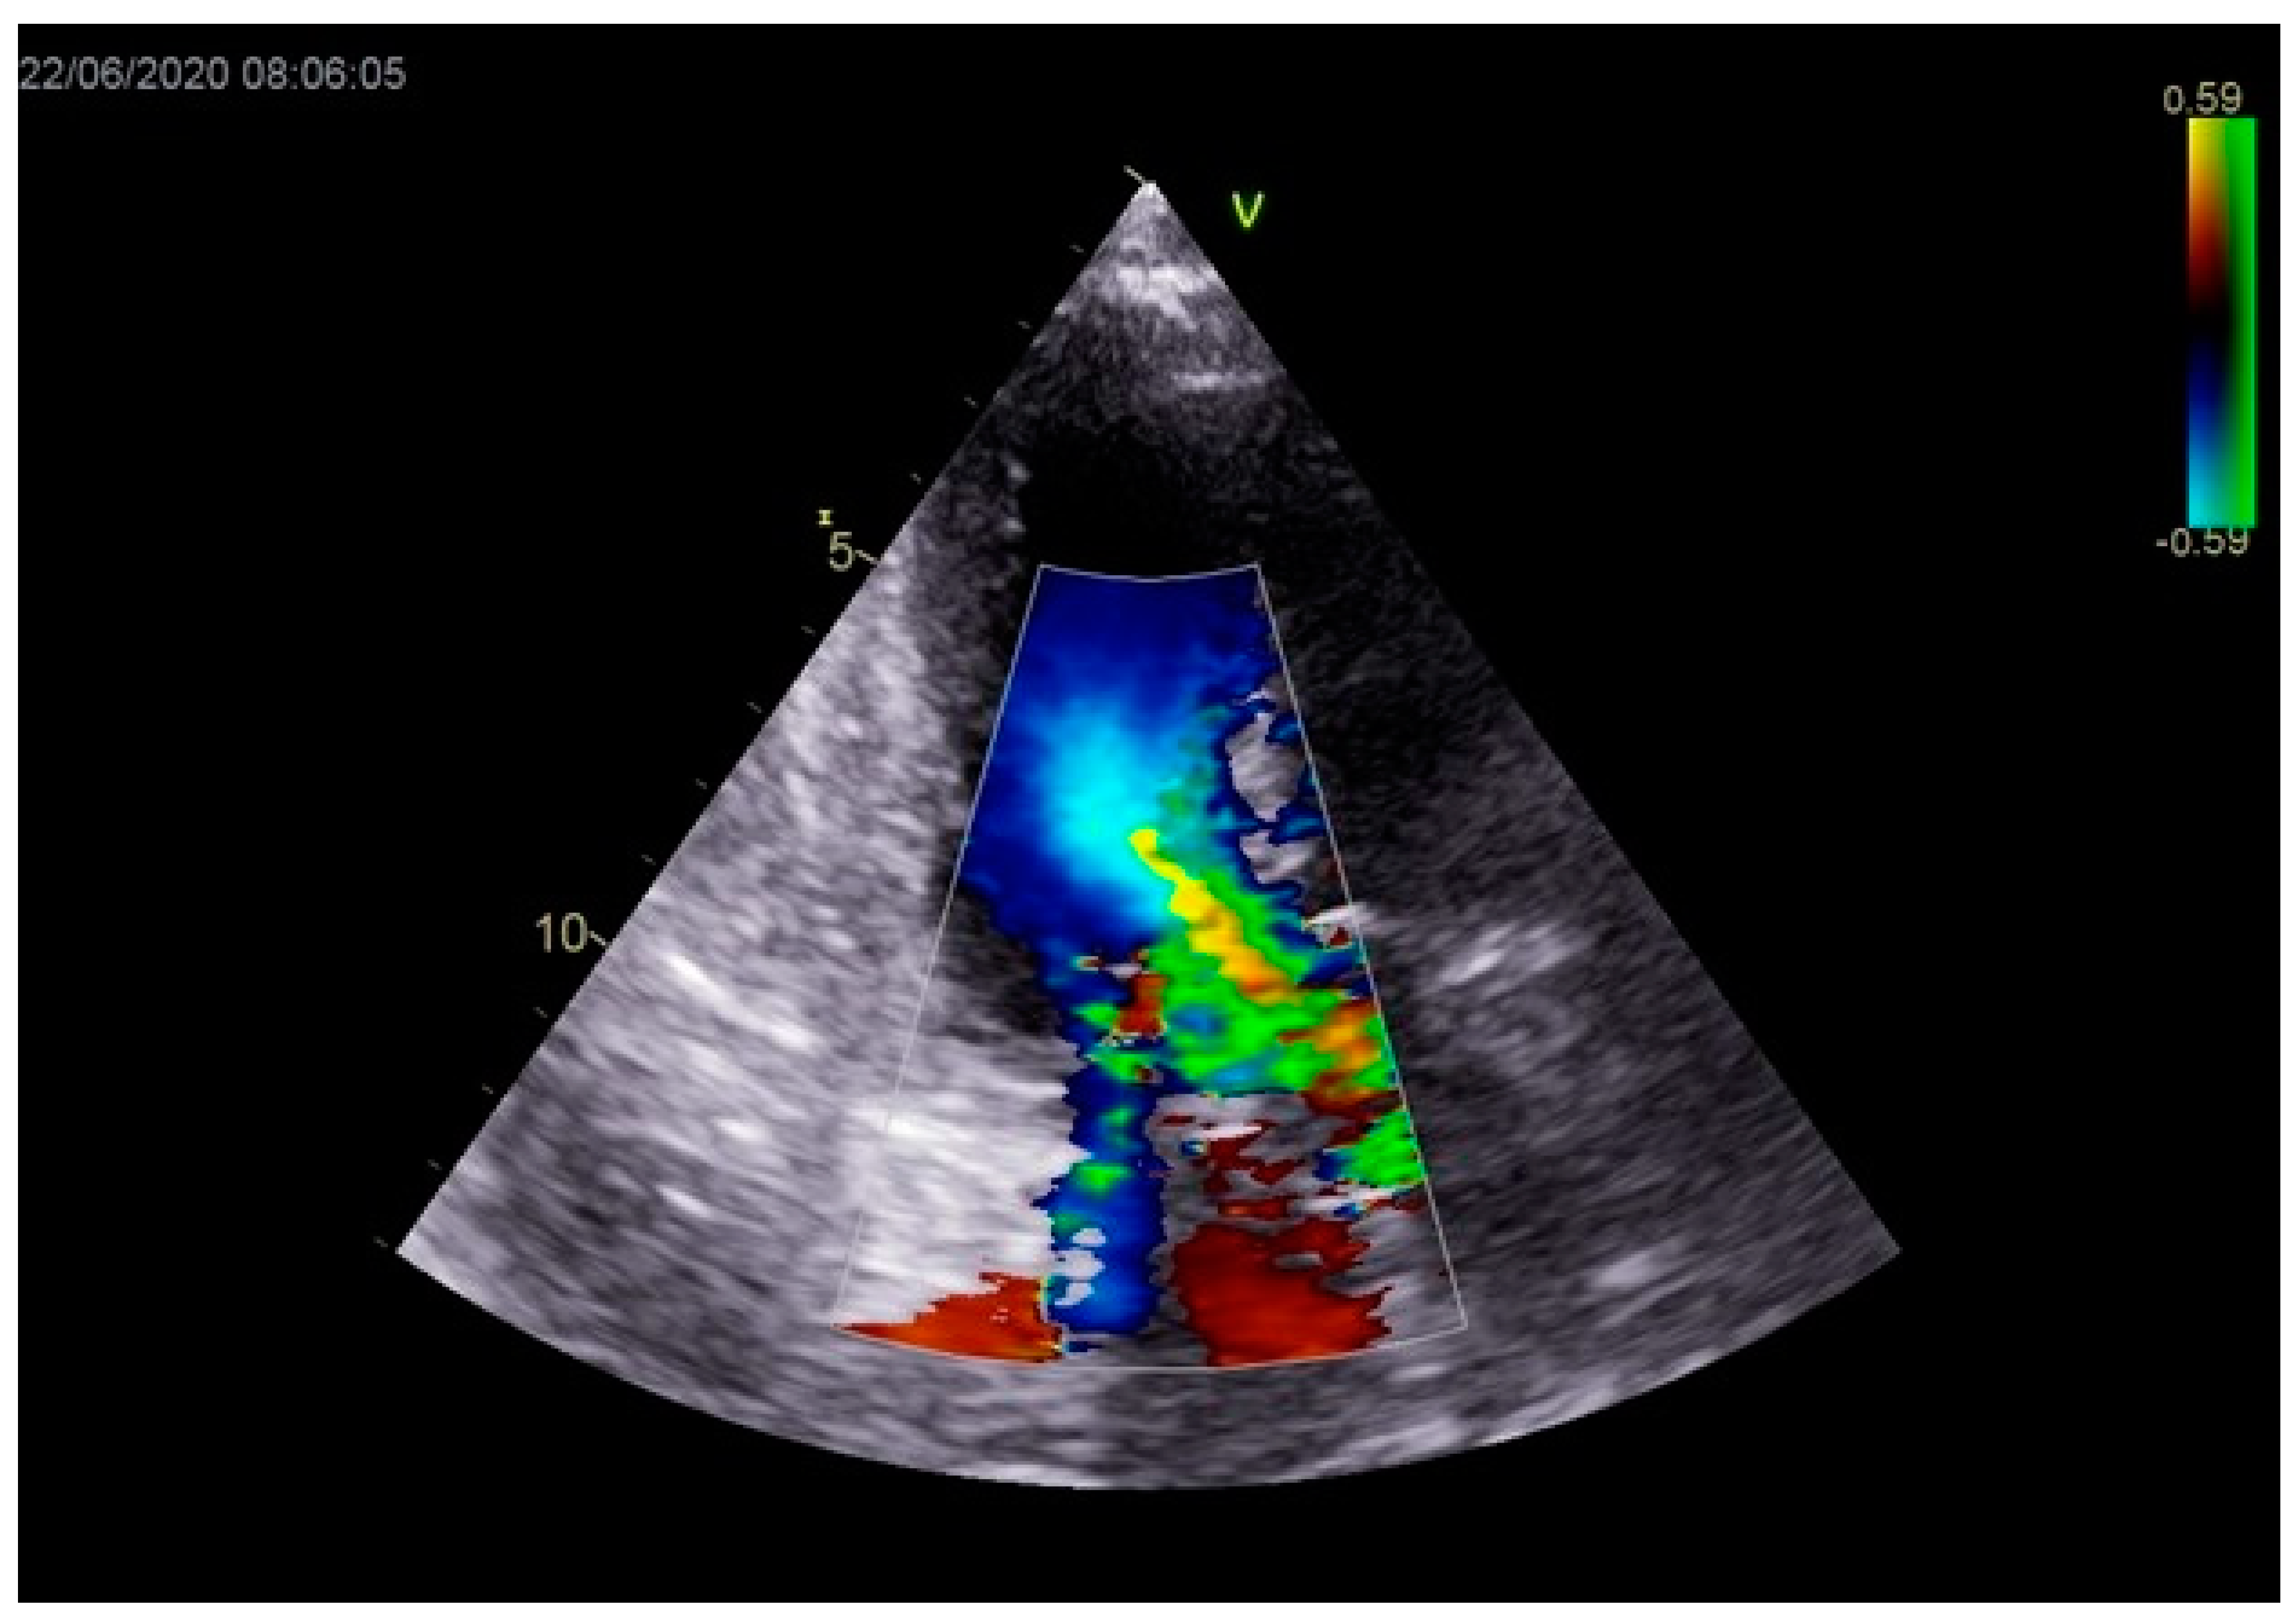

Figure 3.

Echocardiography registered moderate mitral regurgitation (d—LVOT, e—mitral regurgitation).

Stabilization was achieved gradually, and vasopressor and inotrope support were excluded. By the second day of hospitalization, sedation was stopped, and the patient was alert and responsive. Invasive mechanical ventilation was no longer necessary, and the patient was successfully extubated. On the seventh day of hospitalization, a control echocardiographic examination registered inferior wall akinesia and hypokinesia apically, anteroseptally, inferoseptally, anteriorly, and inferiorly with an estimated LVEF of 52%. No significant gradients were found above the LVOT and there was no pericardial effusion (Figure 11). Mild mitral regurgitation was also registered (Figure 12), but there was no systolic murmur over the precordium.

Figure 12.

Mild mitral regurgitation was registered with color Doppler echocardiography.